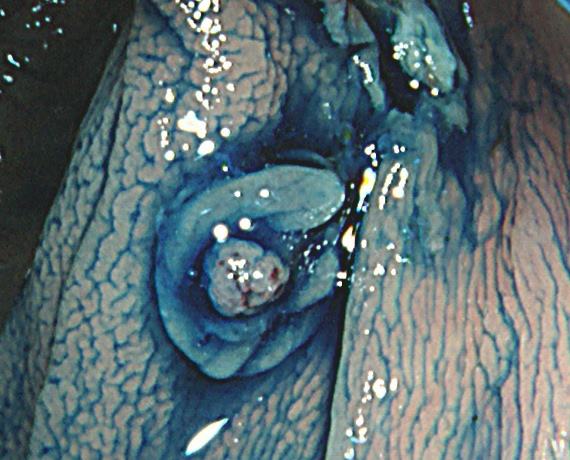

実際の「Extended Cold法」の模様を紹介します

しかしながら・・・いつも、このような綺麗な「目玉焼き」ができる訳ではありません。実際はスネアー(ワイヤー)が、うまくかからずに「分断」「分割」になったり、カンシ(ジャンボ・バイオプシー)を併用することも多いです。

患者さんの立場で言うなら、「ポリープ切除後の写真」をしっかり確認することが最も重要です。

重要なのはポリープではなく右の写真!!!